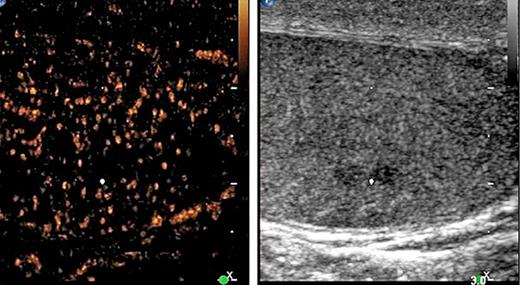

1st patient: this 43-year-old man presented with left-sided testicular discomfort. Contrast-enhanced scrotal ultrasonography demonstrated unspecific irregularities of the intratesticular echo pattern (Fig. 1). Scrotal MRI was likewise inconclusive. The classical serum tumour markers were all in the normal range. Therefore, the patient was put on a surveillance schedule. As the patient moved to another city, he was lost to follow-up. But, enquiries disclosed that orchiectomy for classical seminoma (pT1, clinical stage [CS] 1) was performed on him at another institution 4 months after our primary assessment. The serum level of miR371a-3p at the time of primary examination was RQ = 39.45 which is much higher than the normal range. Knowledge about the elevated miR-level would clearly have changed decision-making. No follow-up measurements of miR371a-p were available.